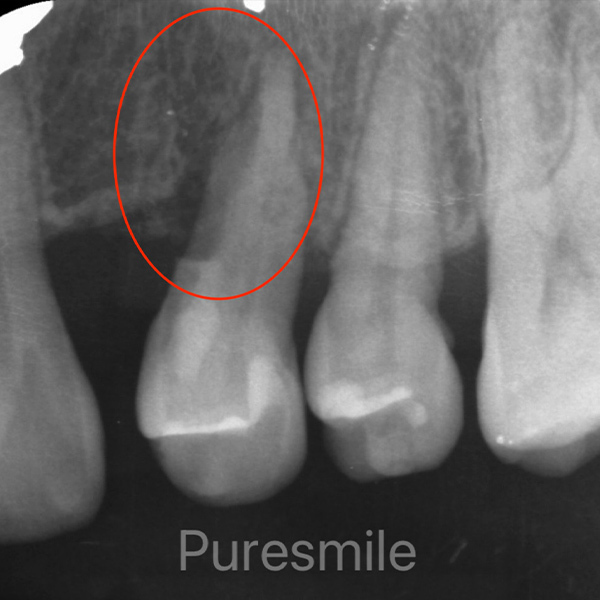

歯周組織再生療法の症例

After

千葉市若葉区の歯周組織再生療法

57歳 女性

歯周組織再生療法

治療の期間・回数:10日間、2回(手術と抜糸)

※この患者さまは矯正治療も平行して行っているため、トータル2年間、25回

治療の価格:約10,000円(税込11,000円 )※健保で対応

治療のリスクや副作用:ご自身でのプラークコントロール、及びメンテナンスをしないと治療は成功しません。外科処置なので他の歯科での外科処置、例えば抜歯のときと同じリスクがあります。(腫れたり、痛んだりなど)喫煙者は適応不可です。(成功率が低いため)

場合によって2週間くらい顔面皮膚にアザができます。これは、時間の経過とともに消えますのでご安心ください。定期管理しなかったり、元々の歯肉の厚みが薄いと歯肉退縮が起こることがあります。